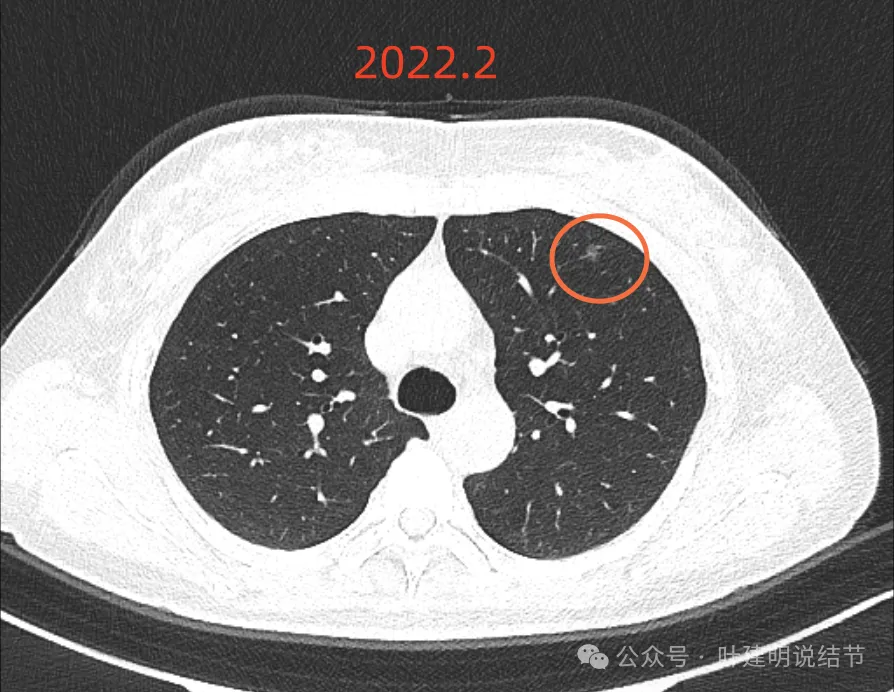

最后来看2024年9月,也就是叫停手术后2整年之后复查的情况:

仍说不上有明显进展,如果将这几次的放在一起来对照,就会更加直观:

病灶基本上没有明显变化。当然不必过于在意具体大小有没有几毫米的差别,也不必在意具体CT值有几十或百把的区别,微细的差别不影响临床决策,也就是说改变都不足以让肉眼发现的,怎么会影响预后呢!

我看了你2022年2月时的片子,以及某医院建议你手术说有进展时的2022年5月时的片子和2023年8月复查时的片子,再对比2024年9月时的影像,总体上明显点的病灶仍是这三处。首先均仍是纯磨,有的似有微血管进入或穿行,但磨玻璃成分密度很淡,而且大小无明显进展。至于右上病灶是否有缩小好转,感觉上右上的与右中叶的都略显淡了点,我怀疑还是扫描条件不一的关系,本身又是非常小而淡的病灶,可比性稍差,并不能说明必是有吸收好转。但肯定说不上有进展,风险仍是低的,半年或一年复查随访(个人倾向可以年度复查)总归不至于会耽误病情。意见供参考!